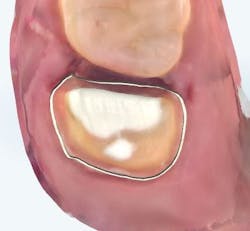

The carious tissue was removed, followed by the endodontic procedure and subsequent placement of the build-up. Despite the deep extent of mesial decay, a clear and accurate scan was achieved (figure 2).

The iTero scanner was able to clearly define the delineation between the soft and hard tissue as can be seen in this image of the digital die trim (figure 3). Radiographs were captured on delivery revealing a clinically acceptable outcome for the patient (figure 4). Direct restorations were completed on teeth Nos. 3 and 4 during this visit.